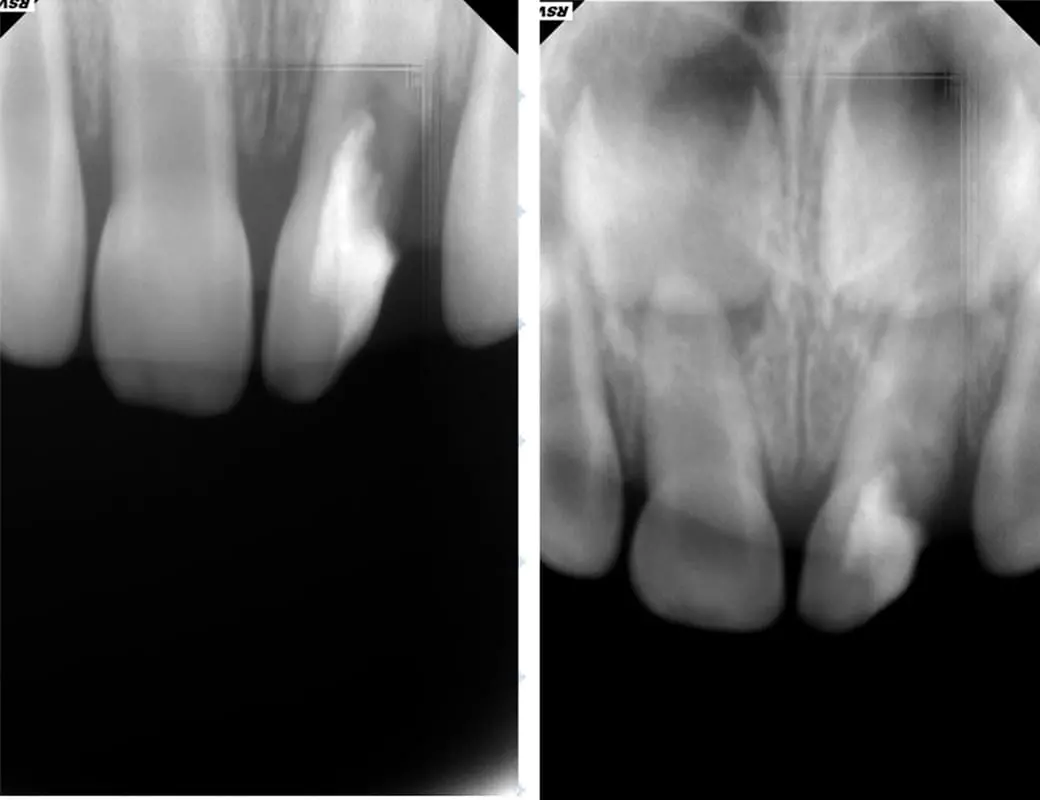

Травма - те, що може статися з будь ким і в будь який момент. А особливо це стосується дітей, які починають активно освоювати навколишнє середовище. Тому знати і вміти зреагувати на травму тимчасового зуба є стратегічно важливим для дитячого стоматолога.

Нерідко, на жаль, трапляються ситуації, коли діти травмують тимчасові зуби. В такому випадку часу на роздуми, як правило, не так багато. Рішення потрібно приймати швидко, часу на підготовку, як правило немає. Саме тому дитячому стоматологу потрібно розуміти, що потрібно робити, а що робити не потрібно. Травми коронкової частини і кореня, навколишніх тканин - що, як і коли робити? В якому випадку терміново втручатись, як коли спостерігати.